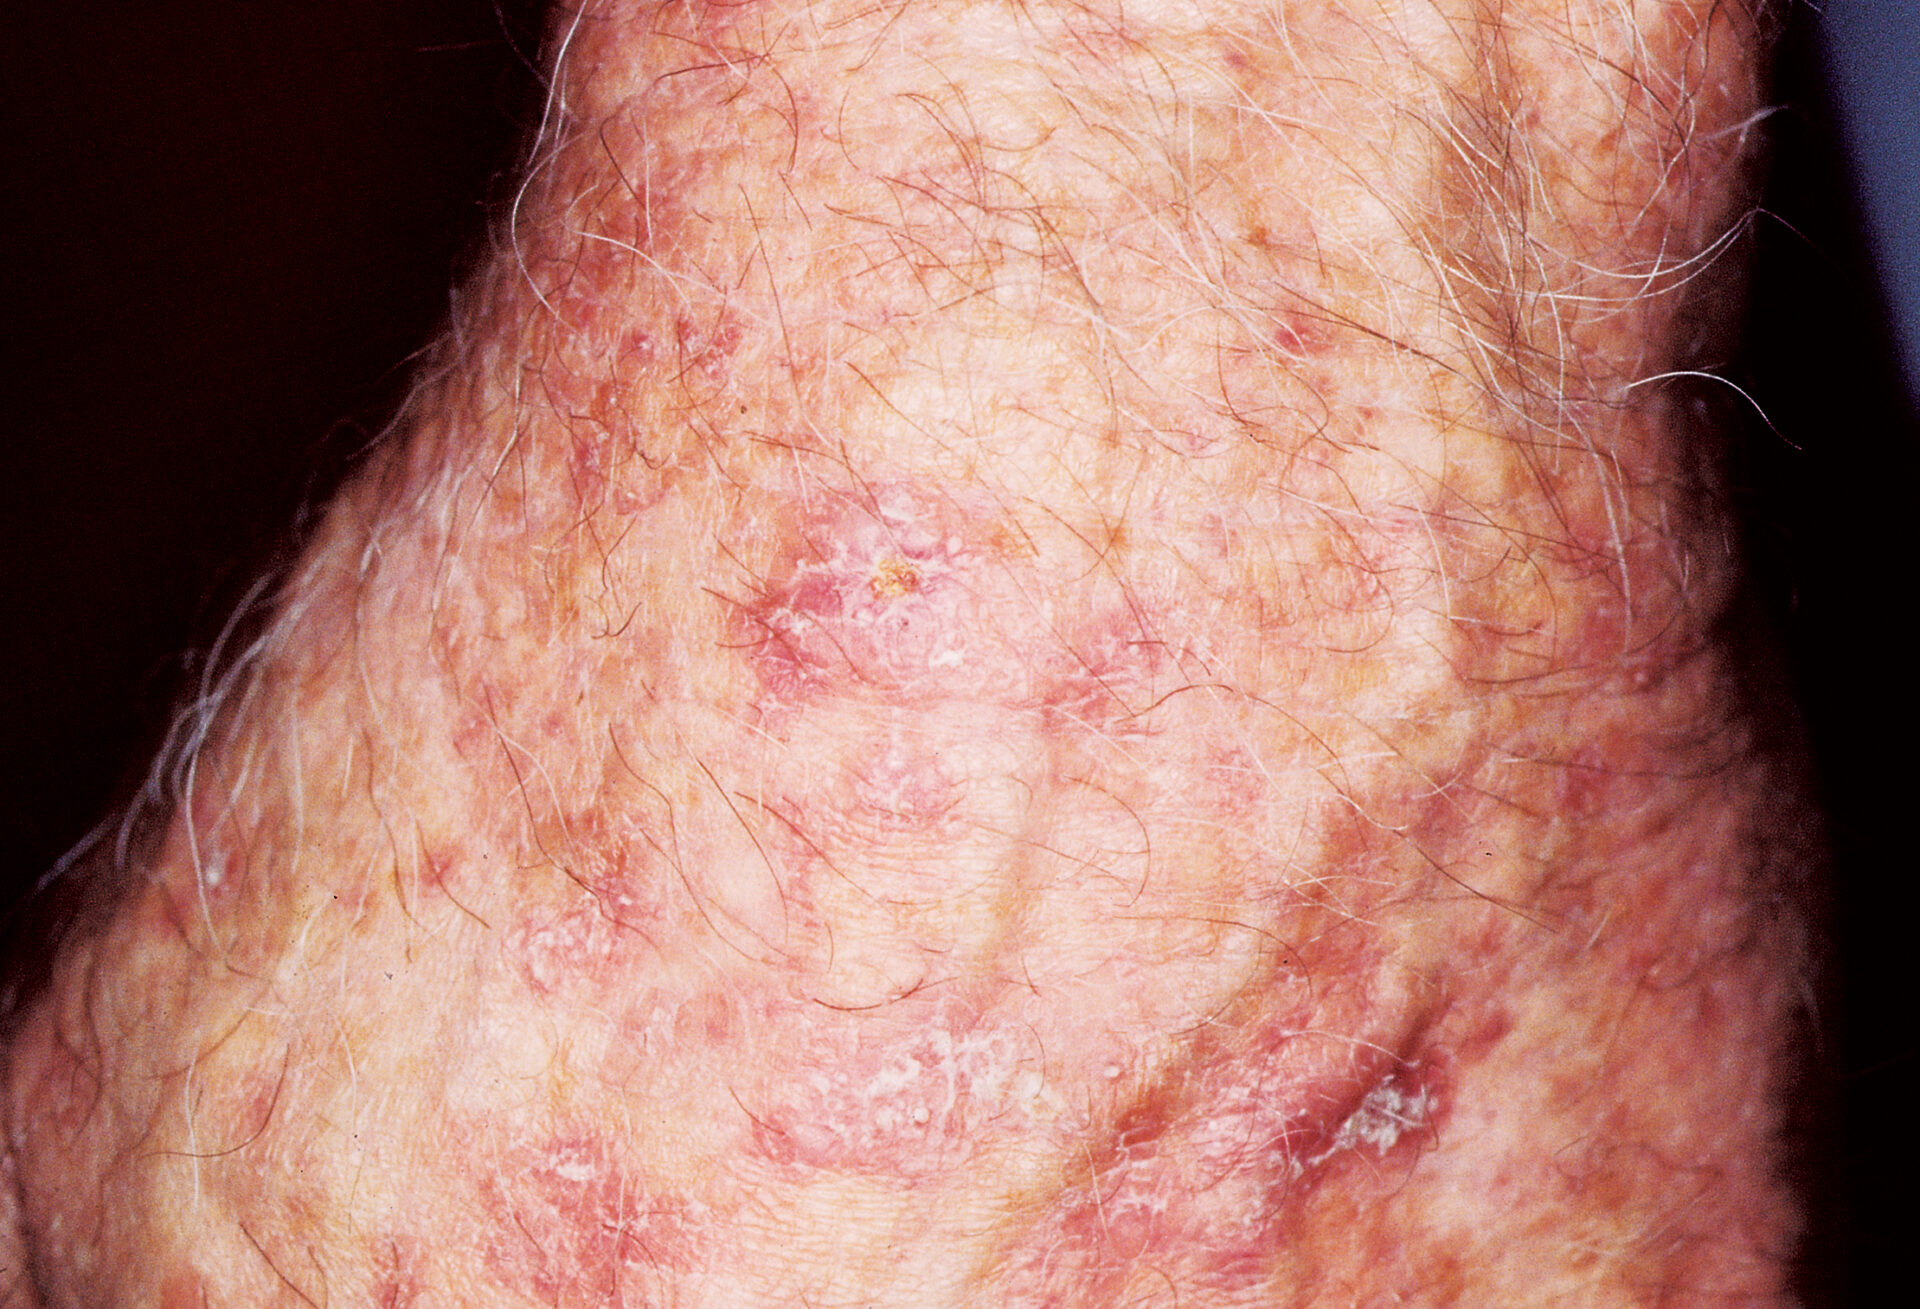

Squamous Cell Carcinoma (SCC) Photos

Squamous cell carcinoma on the neck. Photo: International Skin Imaging Collaboration at isic-archive.com